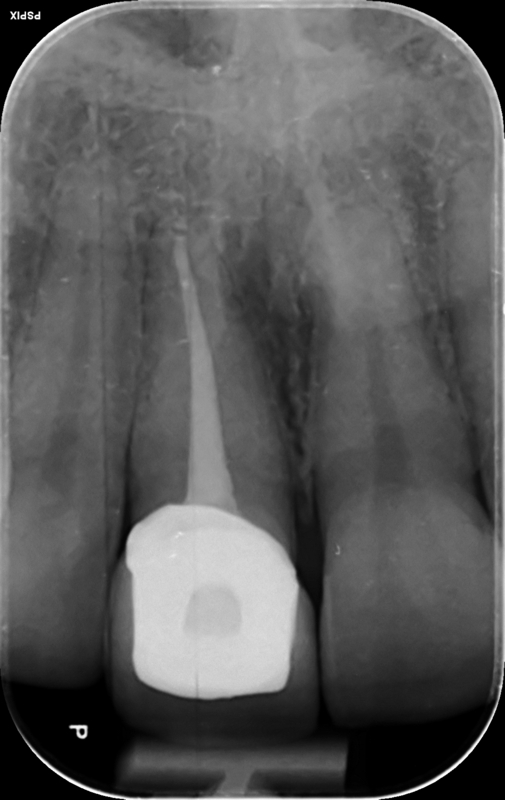

Root canal treatment and crown upper right central incisor.